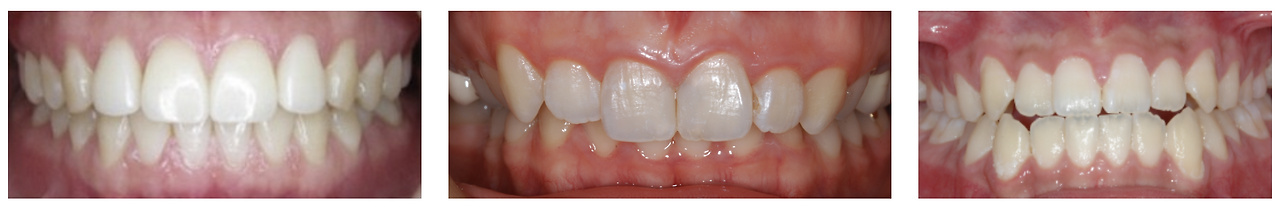

정상 교합 / 과개교합 / 반대교합

실제로 안면비대칭 교정으로 하악의 위치가 앞쪽으로 이동하면서 거북목이 개선되어 경추 커브가 바뀌고 아래턱의 위치가 앞으로 이동해서 치아의 교합까지 정상 교합에 가깝게 변화가 생깁니다.